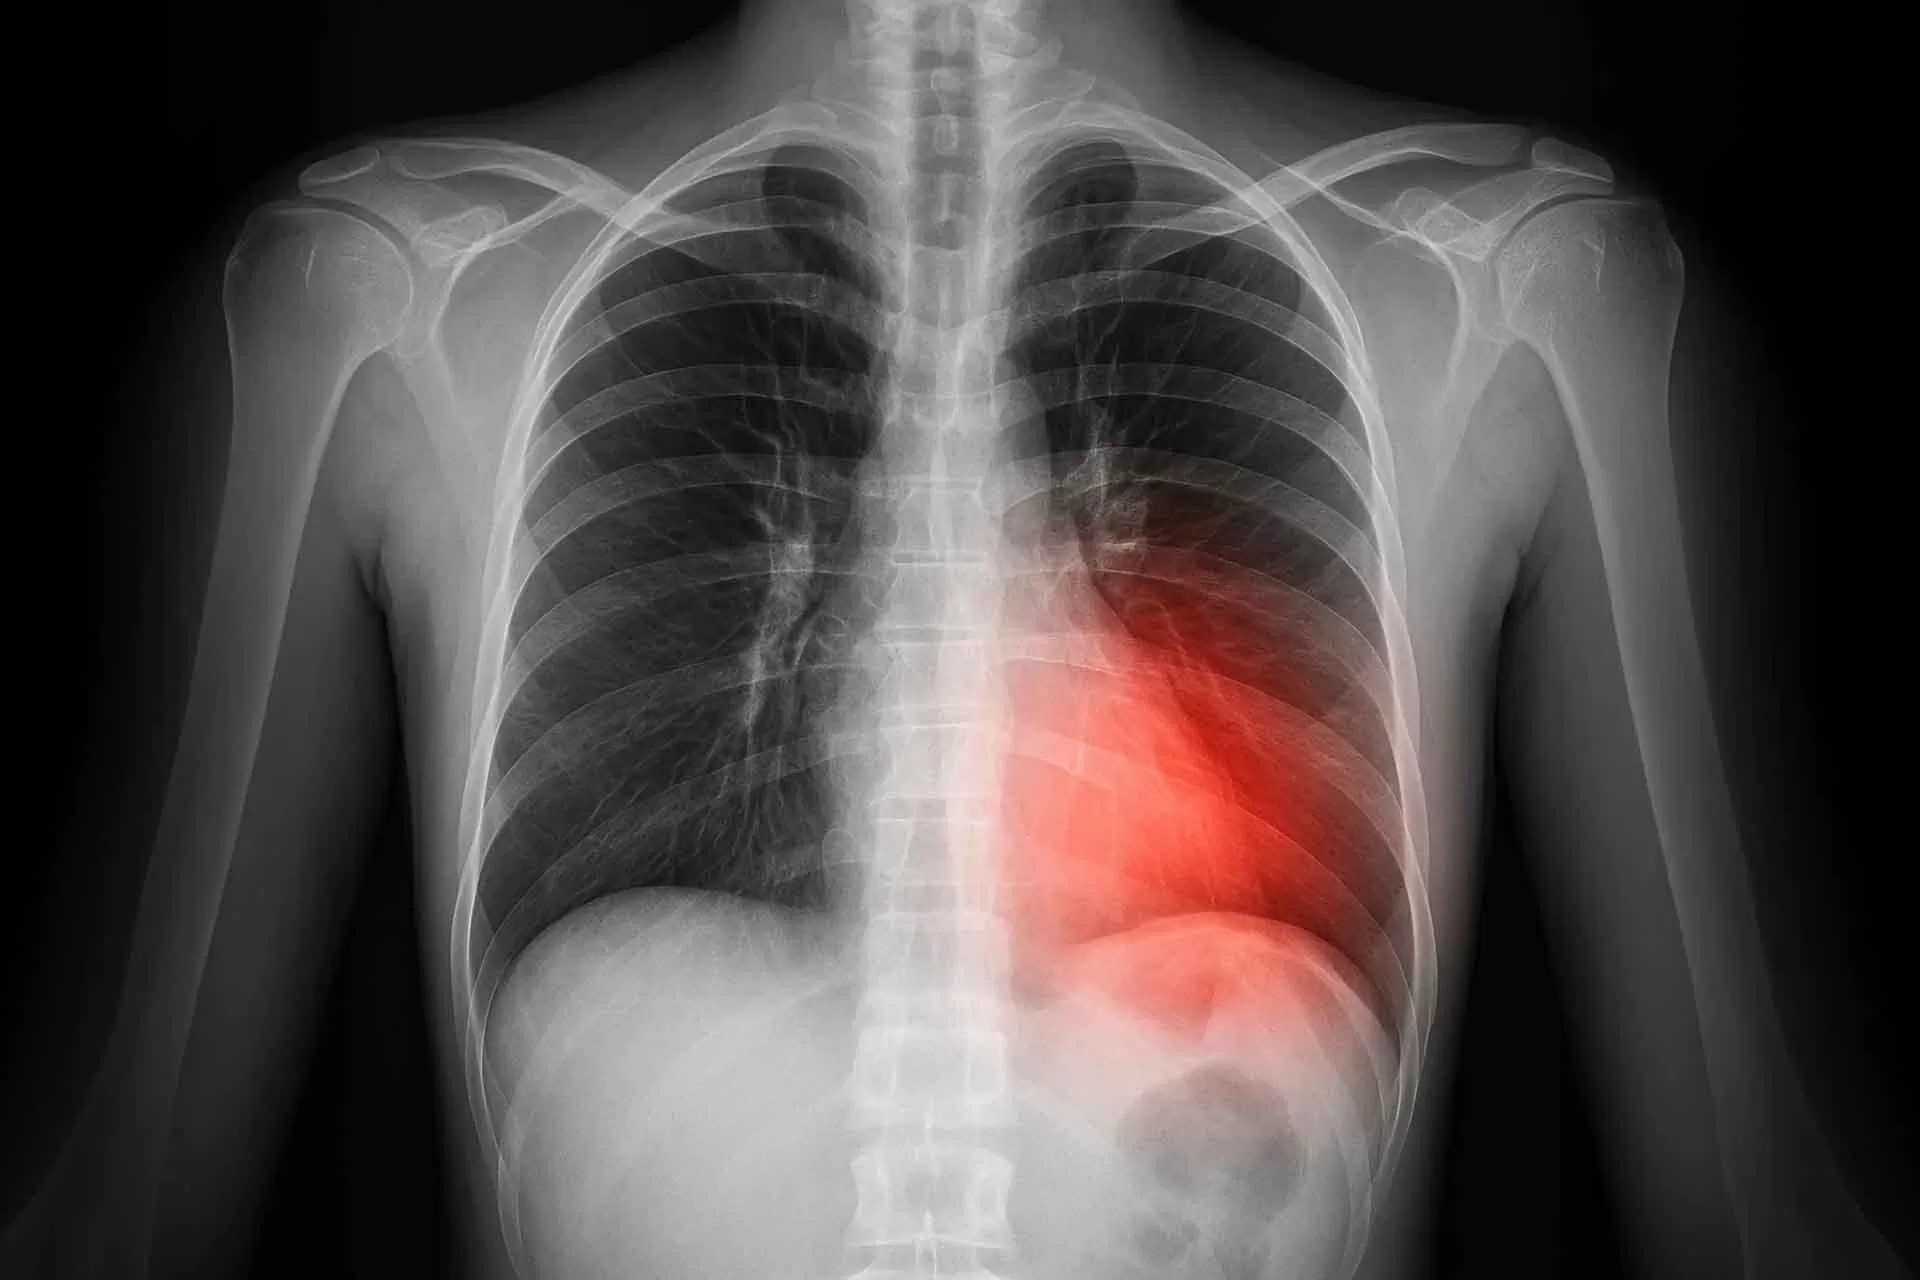

Đáng chú ý, mức độ rủi ro sức khỏe ở những người mang gene này không đồng nhất. Trong số những cá nhân được chẩn đoán mắc hội chứng Birt-Hogg-Dubé, khoảng 37% có nguy cơ bị tràn khí màng phổi. Tuy nhiên, con số này giảm còn 28% ở nhóm chỉ mang gene mà chưa phát triển hội chứng. Tương tự, tỷ lệ mắc ung thư thận ở bệnh nhân có hội chứng là 32%, trong khi chỉ khoảng 1% người mang gene phải đối mặt với nguy cơ này.

Giáo sư Stefan Marciniak (Đại học Cambridge) cố vấn danh dự tại Cambridge University Hospitals NHS Foundation Trust và Royal Papworth Hospital NHS Foundation Trust, nhấn mạnh việc phát hiện sớm là yếu tố then chốt, đặc biệt với hai nguy cơ lớn là tràn khí màng phổi và ung thư thận. Ông lưu ý, các vấn đề về phổi thường khởi phát từ 10-20 năm trước khi các dấu hiệu ung thư thận xuất hiện, do đó, sàng lọc định kỳ có thể giúp phát hiện và điều trị kịp thời.